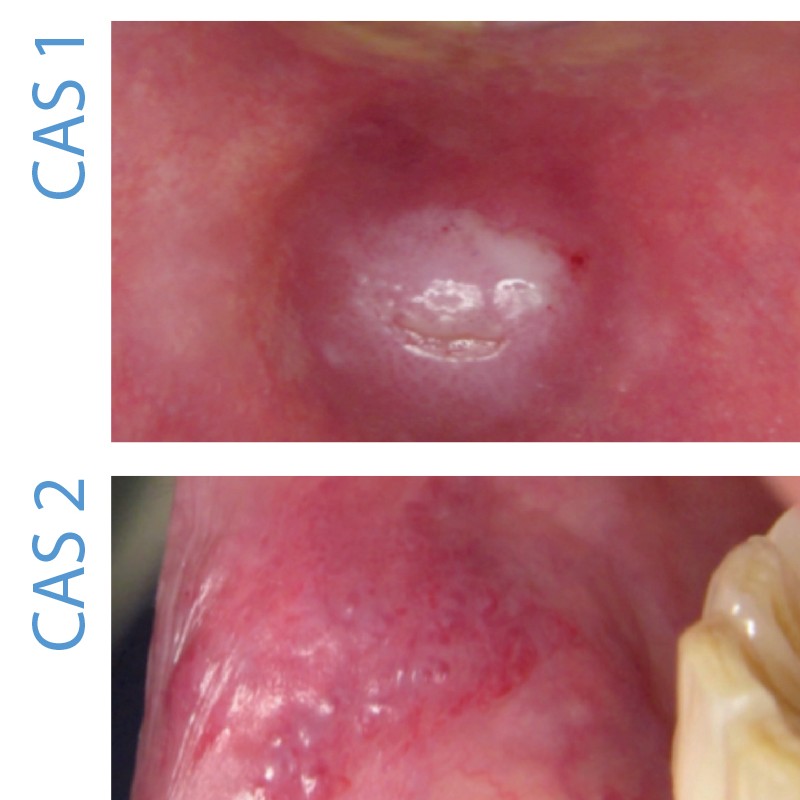

CAS 1

Motif de la consultation.

Patient de 25 ans qui a consulté pour une lésion de la lèvre inférieure.

Histoire de la maladie. Le patient décrivait une tuméfaction labiale évoluant depuis 3 mois.

Interrogatoire. Il précisait que la lésion était apparue à la suite d’une morsure. La lésion augmentait progressivement de volume. Elle gênait le patient qui la mordait fréquemment.

Examen clinique. Il a révélé un nodule indolore, violacé sur la muqueuse labiale en regard de 41-42. Ce nodule était kératinisé en surface et il présentait sur son sommet une ulcération correspondant au bord incisif de la 42. À la palpation, ce nodule avait une consistance molle.

Examens paracliniques. Aucun examen paraclinique ne semblait nécessaire avant l’exérèse du nodule. Un examen anatomopathologique de la pièce d’exérèse a cependant été réalisé à titre systématique. Il a révélé une cavité pseudo-kystique remplie de mucus, bordée par un infiltrat inflammatoire associé à de la fibrose.

Synthèse. Ce cas est un pseudo-kyste salivaire par extravasation (mucocèle) de la lèvre inférieure. Le mucocèle est le plus souvent secondaire à un traumatisme, en général mineur. Le traumatisme entraîne la destruction partielle d’une glande qui va alors sécréter la salive dans le parenchyme environnant. À l’examen anatomopathologique, on ne retrouve pas d’épithélium bordant la cavité. Les vrais kystes salivaires rétentionnels dus à une obstruction du canal excréteur sont plus rares. L’examen anatomopathologique révèle un kyste bordé par une paroi épithéliale. Quelle que soit la forme anatomopathologique, le traitement reste l’exérèse chirurgicale. Les récidives sont exceptionnelles.